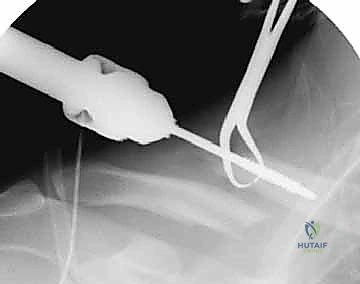

الخلاصة الطبية السريعة: تثبيت كسور الترقوة داخل النخاع (Intramedullary Fixation) هو إجراء جراحي حديث ومتطور، يستخدم مسمارًا أو قضيبًا مرنًا من التيتانيوم لتثبيت عظم الترقوة من الداخل (داخل القناة النخاعية للعظم)، مما يوفر استقرارًا ميكانيكيًا فعالًا وتعافيًا أسرع بكثير من الطرق التقليدية. يتميز هذا العلاج بكونه أقل بضعاً (Minimally Invasive)، حيث يتطلب شقوقًا جراحية صغيرة جدًا، مما يضمن نتائج تجميلية أفضل ويقلل من خطر تلف الأنسجة المحيطة. ويعد هذا الإجراء خيارًا ممتازًا ومثاليًا لحالات مختارة من كسور منتصف الترقوة المنزاحة.

في تقنية التثبيت داخل النخاع، يتم استغلال هذه القناة الطبيعية لتمرير المسمار أو القضيب المرن بداخلها، مما يجعل المسمار يعمل كدعامة داخلية (Internal Splint) تتحمل الأحمال وتشاركها مع العظم (Load-sharing)، بدلاً من تحملها بالكامل كما تفعل الشرائح المعدنية الخارجية (Load-bearing).

هذه هي التقنية المتقدمة التي يتميز بها البروفيسور محمد هطيف. بدلاً من وضع شريحة خارجية، يتم إدخال مسمار أو قضيب مرن (مثل مسمار التيتانيوم المرن TEN أو مسامير مصممة خصيصًا للترقوة) داخل تجويف العظم (القناة النخاعية).